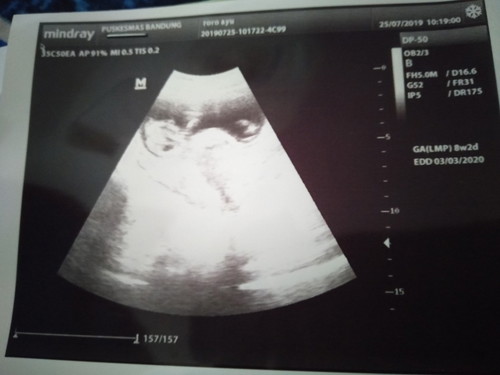

Kayaknya Dr hasil usg hpl 3.3.2020 itu bun

Kalau HPL nya tanggal 27/1/2020 haid terakhir nya bulan april bun .. Soal nya itu HPL nya saya.